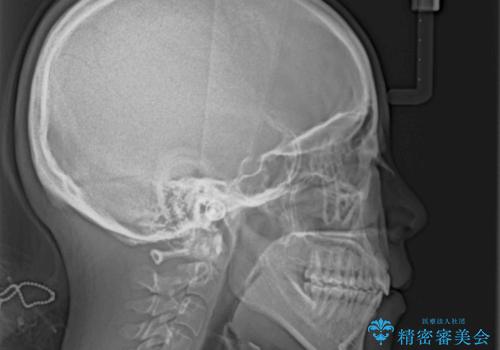

- 口元の突出感と上下前歯のでこぼこを気にして来院された患者様です。

上下前歯部叢生のスペース獲得のため、上下顎左右小臼歯各1歯(計4本)を抜歯して、矯正治療を行うこととしました。